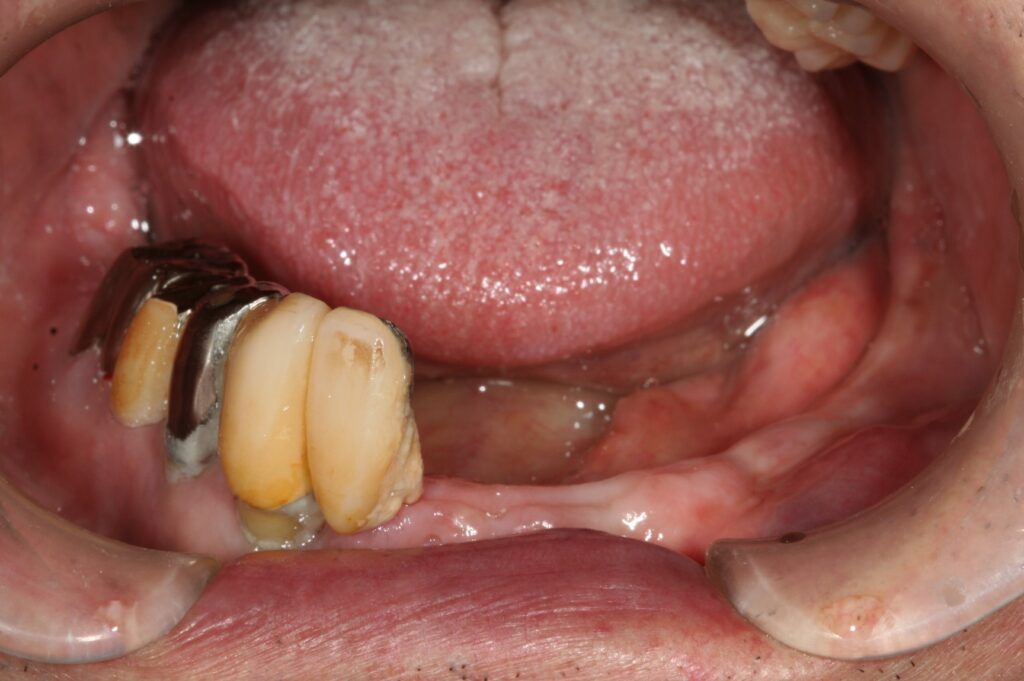

インプラント 2018.06.5 症例紹介 歯が無い部分は取り外しの入れ歯をしてありましたが、固いものが噛めないということでインプラントをし固定式の被せ物にしました。 症例紹介 ランニング前の記事 歯 を守る次の記事